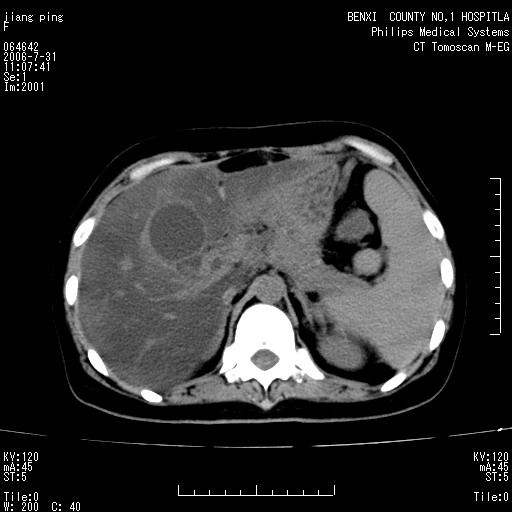

以下是引用晓杰在2006-8-1 9:01:00的发言:[br]支持营养不良导致脂肪肝。[br]胰头增大界限不清,考虑为胰腺炎破坏十二指肠粘膜、肠壁增厚、肠腔狭窄,并与胰头粘连所致

以下是引用jiajie在2006-7-31 20:34:00的发言:[br]支持营养不良导致脂肪肝。[br]胰头增大界限不清,考虑为胰腺炎破坏十二指肠粘膜、肠壁增厚、肠腔狭窄,并与胰头粘连所致。